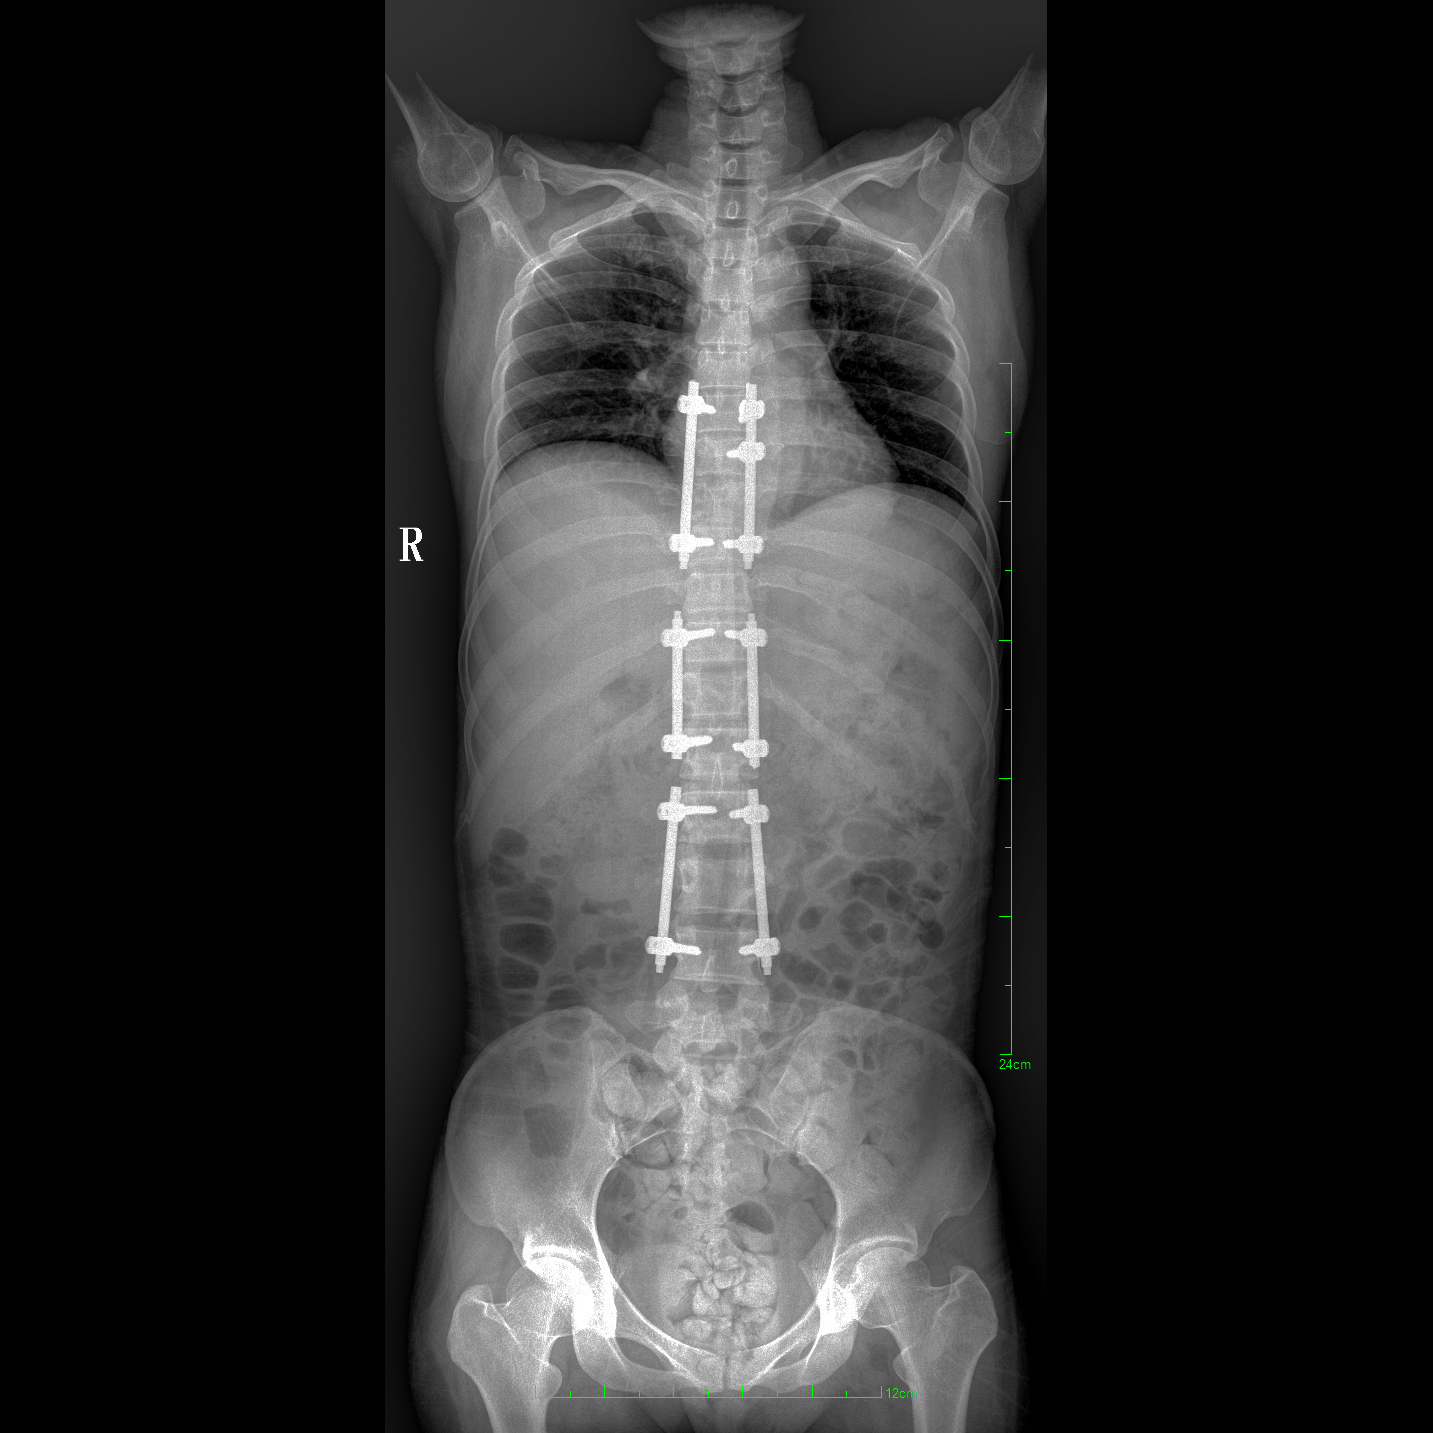

17"*34"有效視野,一次成像不拼接。相較于多張攝影再軟件拼接的DR設備,PLX8600解決了拼接圖像存在密度不均勻,拼接處圖像配準和放大效應等問題,給臨床帶來了大視野影像解決方案,可一次性覆蓋全脊柱或雙下肢影像。